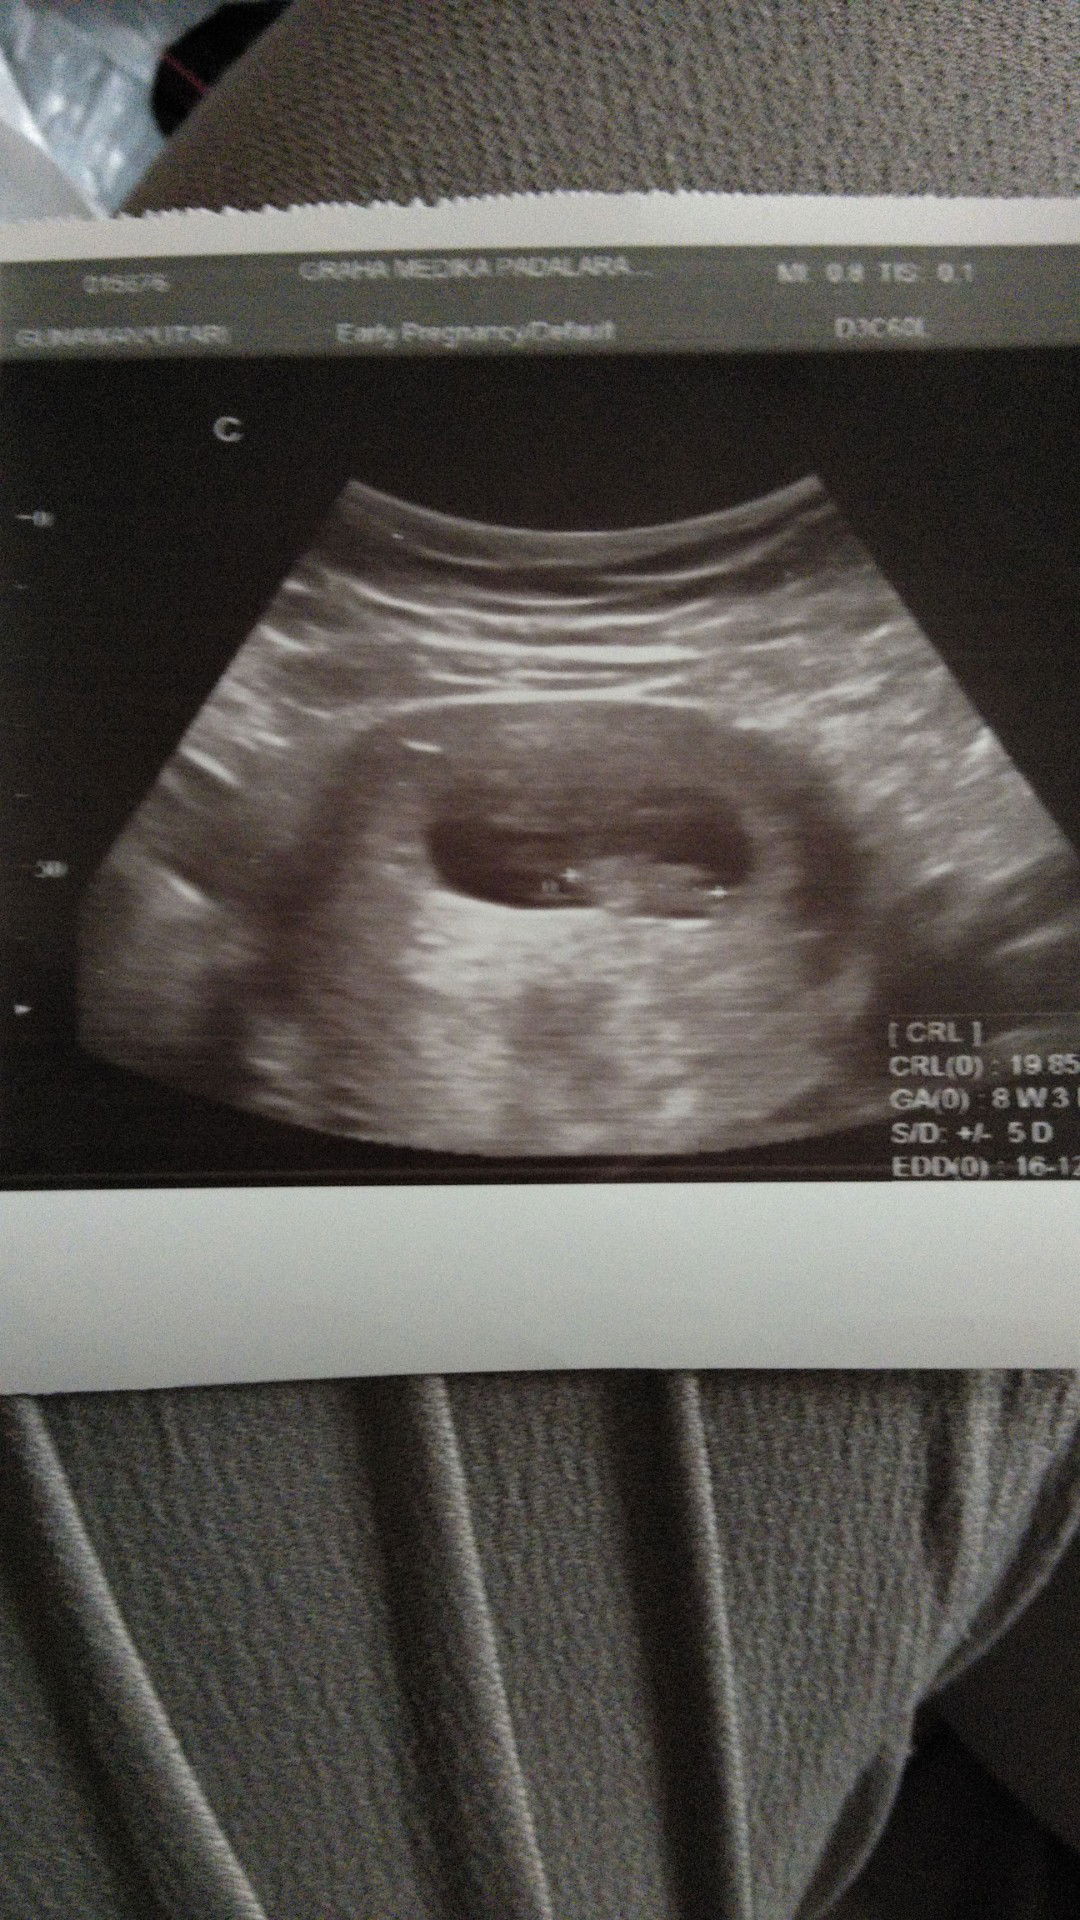

uisa usg dan hpht beda

Bun, mau tanya dong. Disini adakah yg usia usg dan hpht nya bedaa, kemarin saya di usg usia kandungannya 8 minggu, sedangkan kalau hitungan hpht nya 12 minggu. Minta sharingnya yaaaa